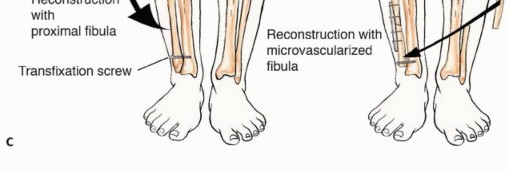

الدراسات التصويرية

تُعد الدراسات التصويرية حجر الزاوية في تشخيص أورام الشظية وتحديد مرحلتها:

- الأشعة السينية العادية (Plain Radiographs): تُظهر الأشعة السينية مدى تدمير العظم، ومدى انتشار الورم داخل العظم، وأي اختراق للقشرة العظمية.

- التصوير المقطعي المحوسب (Computed Tomography - CT): يوفر التصوير المقطعي صورًا تفصيلية للعظم، مما يساعد في تقييم مدى تدمير العظم وانتشاره داخل نخاع العظم. كما أنه مفيد لتقييم امتداد الورم إلى الأنسجة الرخوة المحيطة.

- التصوير بالرنين المغناطيسي (Magnetic Resonance Imaging - MRI): يُعد التصوير بالرنين المغناطيسي الأداة الأفضل لتقييم امتداد الورم إلى الأنسجة الرخوة المحيطة، وتحديد علاقته بالأعصاب والأوعية الدموية، وتقدير حجم الورم بدقة. كما أنه يوضح الامتداد داخل نخاع العظم بشكل ممتاز.

الاستئصال من النوع الثاني (Type II Resection):

- الإشارة: يُستخدم لعلاج الأورام الغرنية عالية الدرجة، والتي عادةً ما يكون لديها تدمير قشري كبير مع امتداد خارج العظم.

- الإجراء: يشمل إزالة الشظية القريبة والمفصل الظنبوبي الشظوي، والحجرات العضلية الأمامية والجانبية، والعصب الشظوي، والشريان الظنبوبي الأمامي بشكل كامل. يتطلب هذا النوع ربط الشريان الظنبوبي الأمامي وقد يتطلب أيضًا التضحية بالشريان الشظوي.

- الحفاظ: لا يتم الحفاظ على العصب الشظوي والشريان الظنبوبي الأمامي.